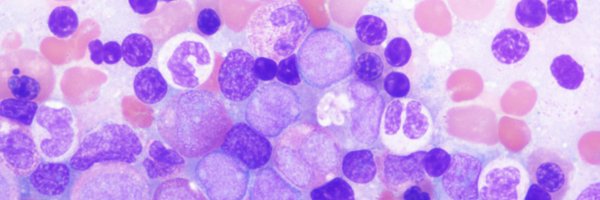

Easy to miss case of intra-vascular large B-cell lymphoma in a renal biopsy. Older pt presented with clinical features of HLH and proteinuria. #renalpath #nephropath #hemepath

Here is one of the cases I will discuss at the upcoming lecture on thoracic IHC @ California Society of Pathologists. Patient w/ lung SqCC & abdominal adenopathy. This is a cell block from lymph node FNA. Enough to call SqCC?? #NatPathPuzzler #PulmPath @PulmPathSoc #PathTwitter

Artifactual kappa light chain restriction in hematogones in a patient receiving Daratumumab (anti-CD38); due to cross-reactivity of fluorochrome labeled anti-kappa antibody with DARA bound to CD38 on the surface of hematogones (PMID: 31313879). #hemepath @NU_Pathology

Incredible example of a TFE3-rearranged PEComa that presented as a colorectal polyp.